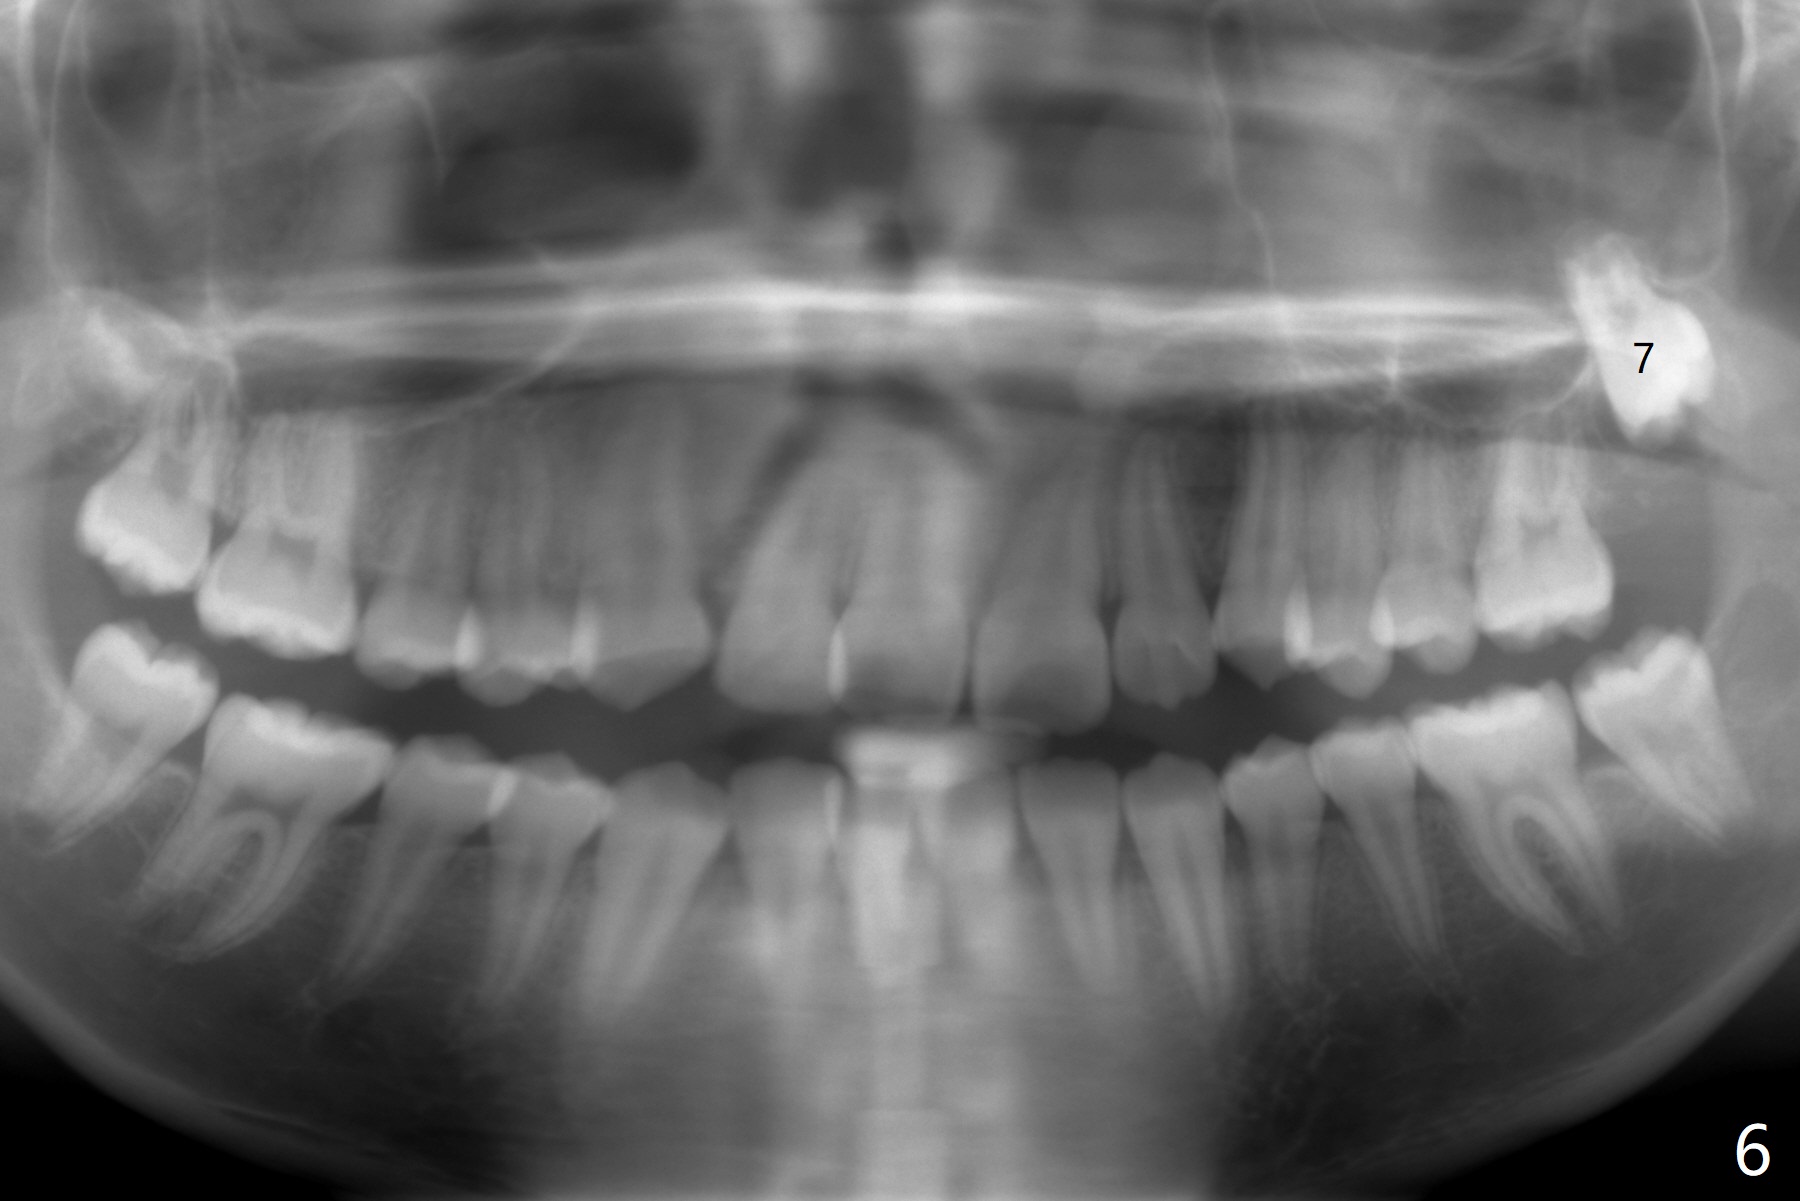

A 12-year-old woman has severe crowding including UL7 impaction (Fig.1-5), finishes non-extraction orthodontics at the age of 15 (Fig.1'-5') and returns for retainer remake at 19 (Fig.1''-5''). Four years post debanding, UL7 (Fig.4') seems to improve its position (Fig.4'').